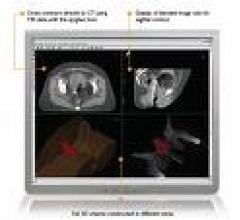

In these challenging economic times, it’s important to make smart decisions when evaluating a 3D advanced visualization system in order to maximize your long-term investment. Budgets and staffing levels are decreasing, while the number of images and functional sophistication needed to analyze those images are increasing.